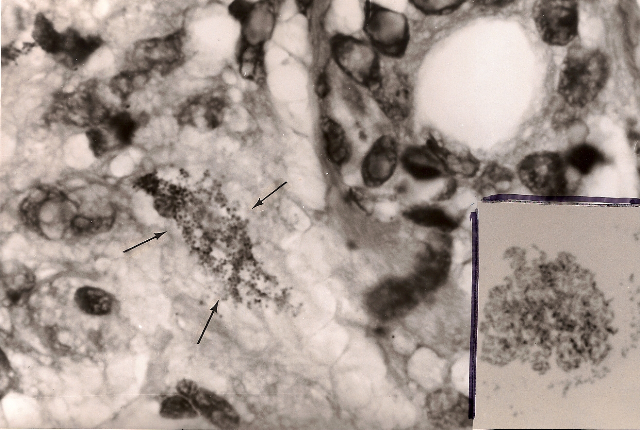

Figure 2. Hodgkin’s lymphoma of the skin. Arrows point to a large collection of minute granules and coccoid forms in the deep dermis. Fite (acid-fast) stain, x1000, in oil. Insert shows appearance of Propionibacterium (Corynebacterium) acnes bacterial cultured from the skin lesion. Ziehl-Neelsen (acid-fast) stain, x1000, in oil Compare the similar size and shape of the bacteria seen in the skin (in vivo) with those cultured in the laboratory.